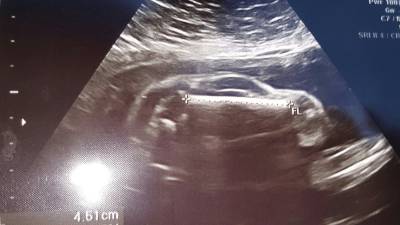

Lejos de parecerse a un bebé, la pantalla mostraba lo que parecía ser un auto deportivo dentro del vientre de la mujer, que tenía 24 semanas de gestación.

La imagen del ultrasonido mostraba una misteriosa silueta con ruedas, un techo inclinado, una ventana e incluso algo que se asemeja a un pequeño volante.

La curiosa imagen, que se viralizó rápidamente, fue compartida por el padre del bebé en Reddit con el siguiente mensaje: “Mi mujer está embarazada de un auto deportivo”.